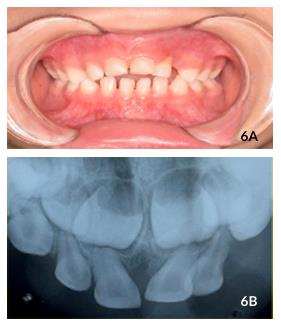

also observed (Figure 5A). Besides, dental biofilm accumulation, redness and swelling in the gingiva inserted around tooth #62, with gingival recession at the cervical level due to occlusal interference, grade I mobility and external root resorption was noted (Figure 5B). On radiographic examination, no signs of periapical and periodontal lesions in tooth #61 was observed. The patient was asymptomatic and there was no need for intervention. On 12-month clinical and radiographic follow-up, the patient returned for a new evaluation and was noted to have the same characteristics as the last follow-up (Figures 6A and 6B).

The child's mother reported that the child still uses a bottle and pacifier and does not feel discomfort in tooth #62. Again, hygiene instructions and guidance on the child's deleterious habits were given. The

mother received information about root resorption of the upper left lateral incisor, which should be extracted at any sign of inflammation, infection or pain. The patient will continue to be monitored by the Oral Health Program at the Department of Pediatric Dentistry at the State University of Londrina.